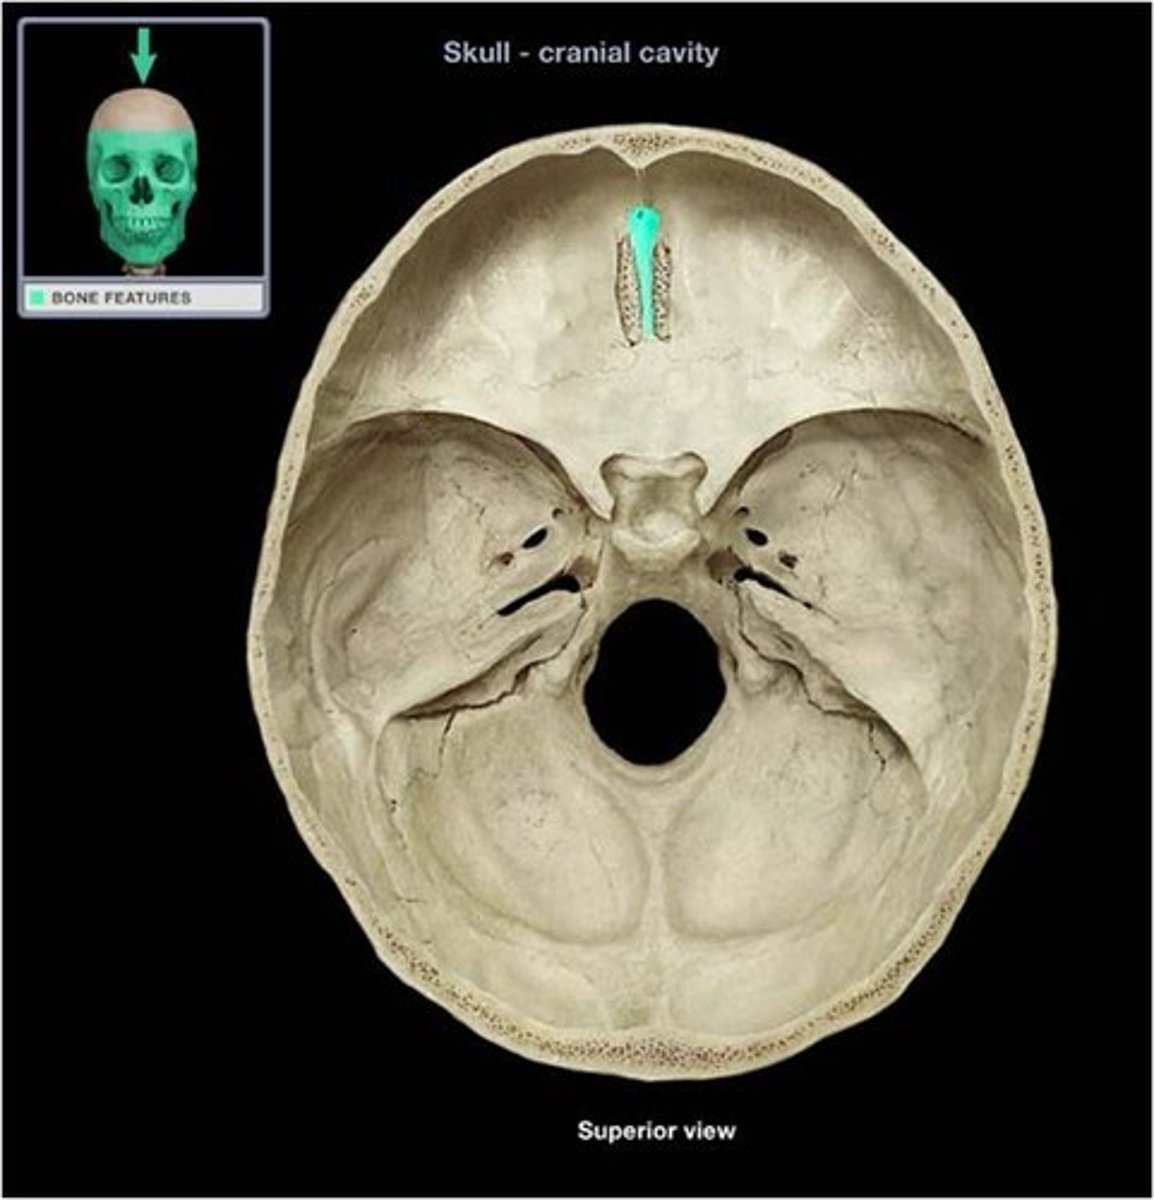

anterior cranial fossa

middle cranial fossa

posterior cranial fossa

Ethmoid bone

ethmoidal notch

orbital plate

cribriform plate

crista galli

perpendicular plate

labyrinths